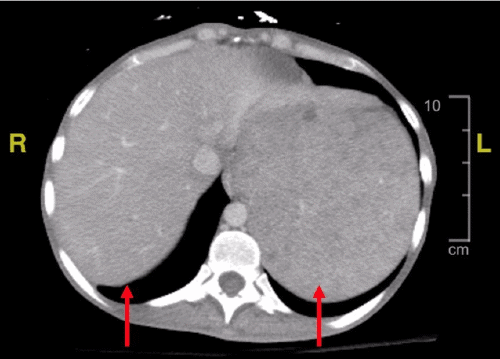

A CT scan of the abdomen (Figure 1) demonstrated marked hepatosplenomegaly (spleen measuring 23 × 15 × 9 cm) and retroperitoneal and mesenteric lymphadenopathy. The differential diagnosis included metastatic lymphoma, disseminated Mycobacterium avium-intracellulare complex (MAC), Castleman disease, and tuberculosis. The patient was started on PCP prophylaxis (atovaquone) and broad-spectrum antibiotics (vancomycin and cefepime). Cardiology was consulted, and a transthoracic echocardiogram showed no acute abnormalities. A multidisciplinary team (hematology/oncology, infectious disease, internal medicine, and general surgery) recommended splenectomy for both diagnostic and therapeutic purposes.

Figure 1. Abdominal and Pelvic CT Imaging with IV Contrast. Published with Permission

(A) Axial view demonstrating hepatosplenomegaly. The spleen measures approximately 23 × 15 × 9 cm at its largest dimensions

(B) Coronal view confirming hepatosplenomegaly.